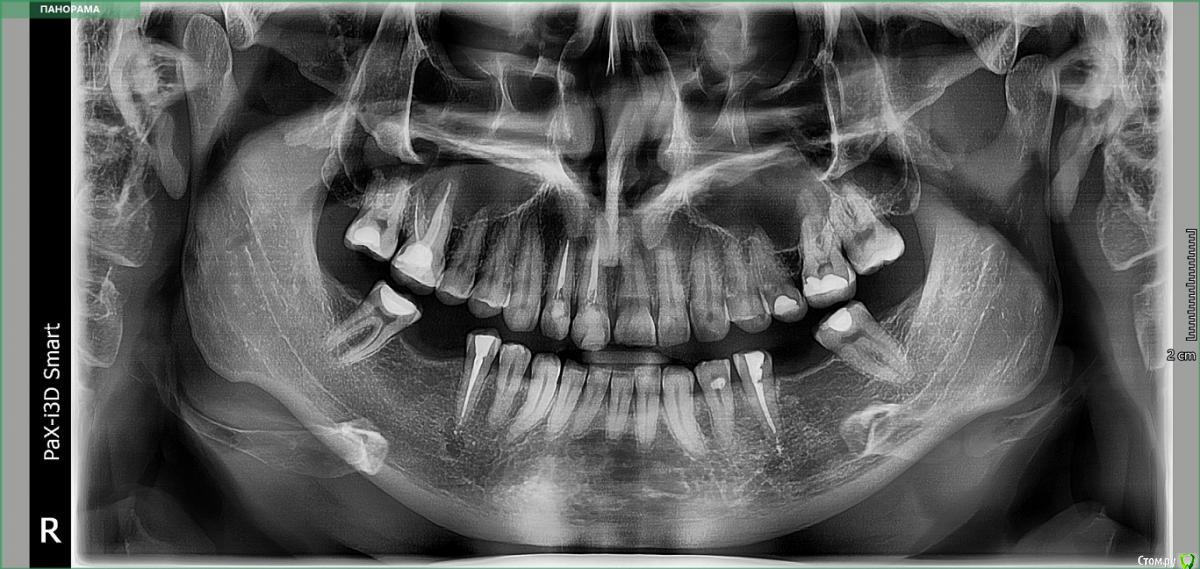

Подскажите пожалуйста, не видно ли периодонтита по снимку - два 5 нижних зуба? 1,2 сверху хорошо каналы запломбированы? Ставили 4 стекловолоконных штифта, готовим нижние зубы для установки двух мостов из диоксида циркония по бокам, на 8 нижних и 10 верхних - керамические виниры. На данный момент беспокоит ноющая боль на 4 или 5 нижнем зубе слева. Первый снимок - до обточки зубов, второй - после обточки и установки штифтов.